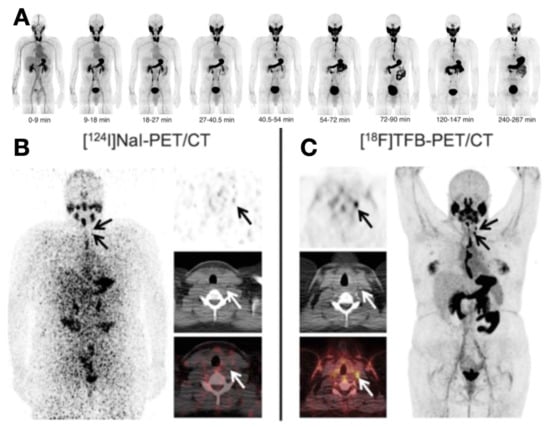

- Samnick, S.; Al-Momani, E.; Schmid, J.-S.; Mottok, A.; Buck, A.K.; Lapa, C. Initial Clinical Investigation of [18F]Tetrafluoroborate PET/CT in Comparison to [124I]Iodine PET/CT for Imaging Thyroid Cancer. Clin. Nucl. Med. 2018, 43, 162–167. [Google Scholar] [CrossRef]